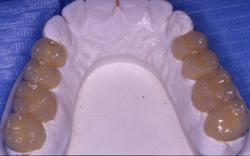

Préparation et empreinte des dents mandibulaires. Les dents vivantes sont conservées pulpées. Les limites des préparations sont supra-gingivales.

Couronnes céramo-céramiques. Réalisation prothétique Claude VALTIN (Paris).

Les 14 Couronnes céramo-céramiques mandibulaires collées.